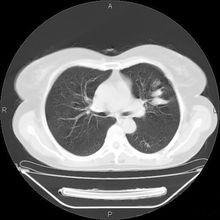

結核性鈣化X線表現(圖1):

肺鈣化灶CT表現(圖2):兩肺瀰漫性粟粒樣影